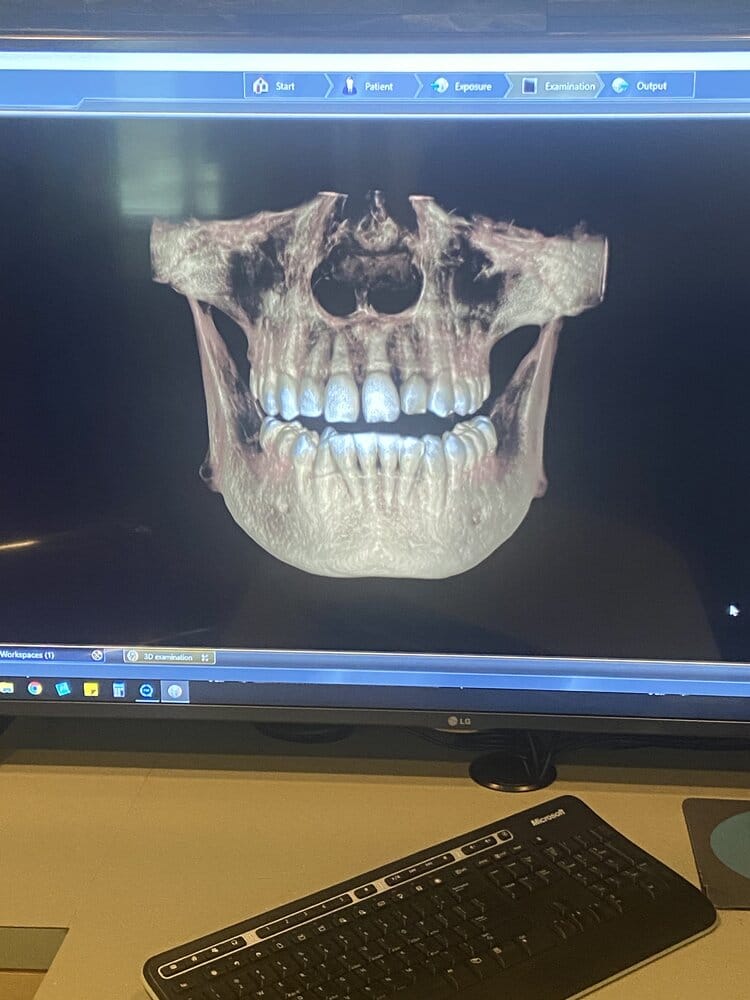

Will need bimax. Im bitting down on a split. My parents fucked me hard and didn’t get me braces when I needed thinking my child hood curry doctor was making shit up about my teeth alignment. Not getting braces caused massive assymetries in my lower third.